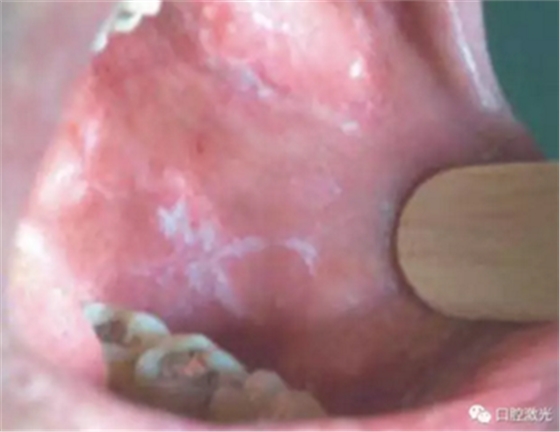

口腔外部检查显示颈部淋巴结没有出现异常,口腔内部检查发现2*4mm溃疡表面呈现淡黄色糜烂,并且周围有1至2mm黏膜红斑。

设置半导体激光,连续模式,功率2W。随后对糜烂区域实施表麻。将激光光纤轻触溃疡区域表面,发射激光。在周围红斑区域采用接近但非接触方式进行激光发射。术后区域的表面呈棕色且干燥,没有碳化的迹象。并且周围黏膜的红斑区域较治疗前得到减轻。